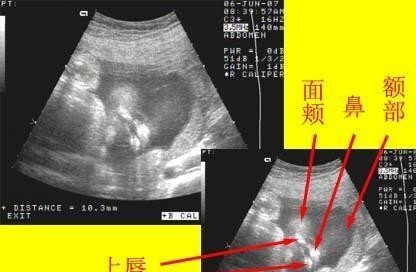

其中到第七周时,胚胎长到1.3cm,手臂和腿开始生出,连手指都开始会分化出;而内部器官如心脏也会分出左右心房。

第八周胎儿定型,头、身体、四肢都已分化完成,胎囊占到宫腔一半,心脏也开始搏动。